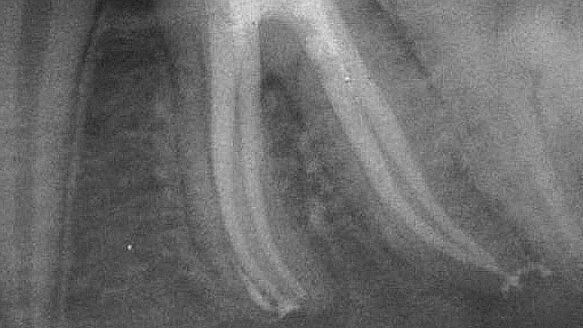

Consequently, the cement is driven laterally against the canal walls throughout the canal’s entire length. Knowing that excess cement will escape coronally rather than being driven apically gives the dentist the ability to thoroughly flood the canal space with cement. When the prefitted master point is then liberally coated with cement and placed into the canal, most of the cement will be driven laterally, with excess cement escaping coronally. The flow of the cement is superior to that of the flow of any thermoplasticized gutta-percha system (Figs. 1, 2). Of greater importance is the fact that it is a room temperature obturation system.